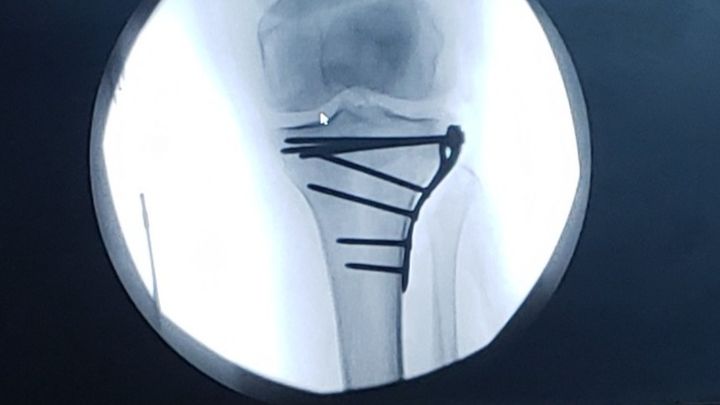

Hi! My name is Debbie Wilds. I am Dawn Dennison's Mother. As you may know, Dawn fell breaking both her legs below the knee. One leg had reconstructive surgery. Both legs are in braces. She will be non weight bearing for weeks. Please help me raise enough funds to cover her monthly expenses for this first month that she will be unable to work. Your generosity will be greatly appreciated.